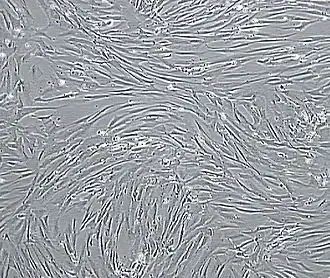

![]() Vascular smooth muscle cells, isolated from human aorta, growing and forming a monolayer in cell culture | |